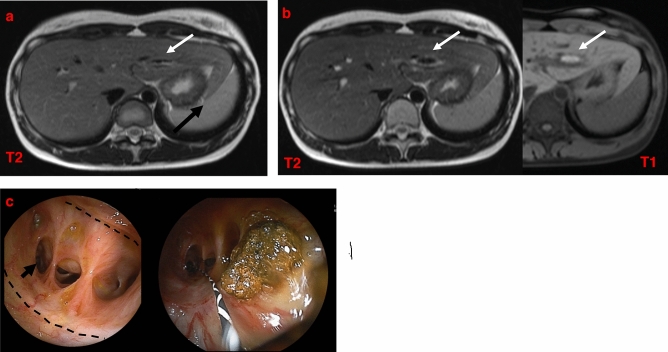

Patients with bile duct strictures were treated by balloon dilation of the stenotic area and/or hepatolithectomy (Table 2). Our hospital began performing DBERC on patients after surgery for CBD in December 2011. Prior to that, patients who developed bile duct and anastomotic strictures would undergo additional operative bile duct plasty and re-anastomosis. After the introduction of DBERC, all patients with postoperative bile duct or anastomotic strictures underwent DBERC. Six of these patients (Cases 1–6) underwent additional surgery (operative bile duct plasty) after the primary surgery followed by further DBERC. Two patients (Cases 1 and 2) underwent DBERC for bile duct strictures after two operative bile duct plasties, and they have been asymptomatic for 23 and 19 months after DBERC, respectively. Of the remaining four patients (Cases 3–6) who underwent DBERC after operative bile duct plasty, two did so several times but eventually required hepatectomy owing to residual hepatolithiasis (Cases 4 and 5), and one of them (Case 4) underwent DBERC again because of bile duct stones (B3) after hepatectomy (right lobectomy). One patient was scheduled for hepatectomy after DBERC due to complete obstruction of the right hepatic duct (Case 3). Another patient (Case 6) underwent radical surgery at the age of four years and another operation for bile duct plasty at the age of eight years (Table 2). Subsequently, she was asymptomatic and there were no abnormalities on MRCP 20 years after radical surgery. Twenty-five years after radical surgery, MRCP identified intrahepatic bile duct stones. We performed DBERC, diagnosed her with bile duct stricture and stones, and performed lithotomy (Fig. 1). The first six cases, except case 3, had been asymptomatic for more than a year after the last treatment (Table 2).

Six patients with anastomotic strictures in the absence of bile duct strictures were treated by balloon dilation of the affected region and/or lithectomy, and symptoms improved in all patients. Six patients were followed-up for 2–98 months after DBERC with no recurrence (Table 4). One patient (Case 20) underwent primary surgery at the age of 23 years and was asymptomatic for over 10 years. Twelve years after radical surgery, abdominal pain occurred, and stones were identified on computed tomography. Anastomotic stenosis was confirmed by DBERC, and lithotomy was performed (Fig. 2). In 6 (cases 3, 4, 5, 7, and 9 in Tables 2 and case 18 in Table 4) of the 23 cases, not all the stones were removed after a single DBERC. In two cases, the stones were completely removed after multiple DBERCs. One case was a B3 stenosis (Table 1, case 9). Another case was an anastomotic stenosis, and the stones remained in the left hepatic duct (Table 4, case 18). Seventeen (74%) of the lumps were removed with a single DBERC. The stones were confirmed to have been completely removed by contrast imaging. In addition, follow-up MRCP revealed no evidence of residual stones.